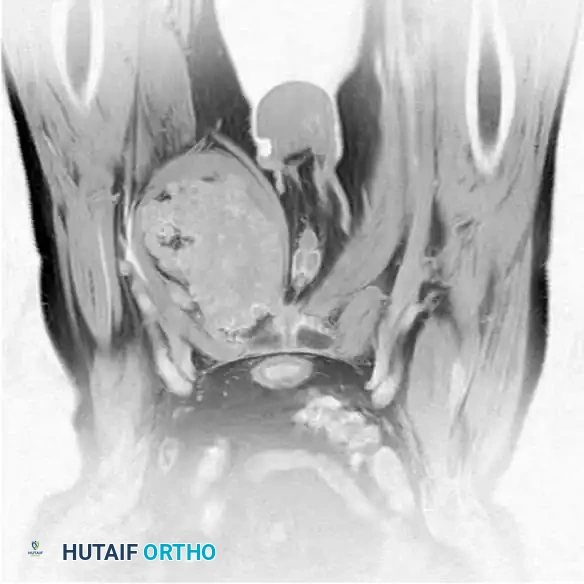

Intraoperative Imaging and Margin Assessment

Continuous intraoperative assessment using fluoroscopy and frozen section pathology is mandatory. The following images demonstrate various stages of complex upper extremity resections, allograft preparations, and prosthetic implantations across the humerus and elbow joint.